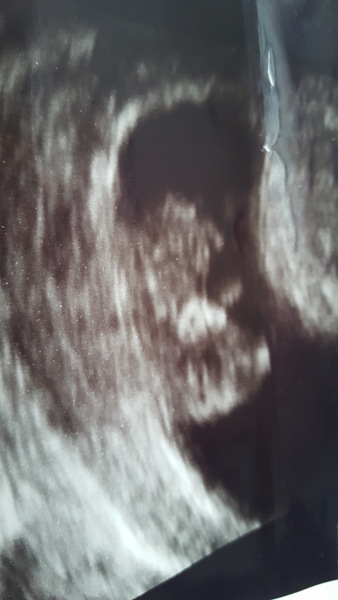

fee1234 · 15/11/2018 18:16

Just had a scan, they are dating me four days ahead which puts me at 11 + 4, look at it sucking its thumb 😩

Feeling relieved everything looks okay.

@fee1234 - what a fab scan!

@fee1234 What a great scan! I have my 12 week on Tuesday at 11+2 ish so it will be lovely if we can see something like that!

Absolutely cracking scan pics today ladies! Congratulations! The thumb sucking is adorable! ❤️